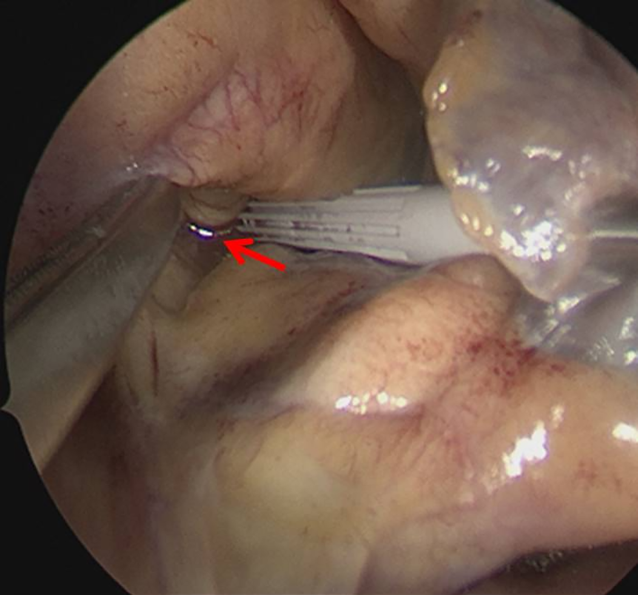

Die weitere Therapie des Patienten erfolgte im engmaschigen Dialog und Konsens der verschiedenen Fachabteilungen – der Herz‑/Thoraxchirurgie, der Intensivmedizin und den endoskopisch tätigen Internisten. Da das Aspirationsrisiko im Rahmen der Narkoseinduktion als sehr hoch eingeschätzt wurde, erfolgte eine „rapid sequence induction“ mit dem Ziel einer möglichst schnellen Sicherung des Atemweges über die endotracheale Intubation. Nach Präoxygenierung mit 15 l Sauerstoff über eine dichtsitzende Maske sowie rascher Applikation der Opioide, Sedativa und schnell wirksamen Muskelrelaxanzien erfolgte die problemlose Intubation ohne Zwischenbeatmung. Bei einem sichtbaren Defekt zwischen den oberen Pulmonalvenen und der Vorhofhinterwand (Abb. 2) entschied man sich für ein primär operatives Vorgehen durch Patch-Plastik mit Vorhofohrverschluss. Der Eingriff wurde in Allgemeinanästhesie unter Einsatz der Herz-Lungen-Maschine durchgeführt. Der Patient erhielt zwei rechtsseitige Pleura- und eine Jackson-Pratt-Drainage, die intraoperativ hinter dem Patch positioniert und postoperativ für insgesamt 3 Tage mit Polyhexanid und Polyethylenglycol gespült wurden.

Abb. 2

Operativer Situs: sichtbarer Defekt (Pfeil) zwischen den oberen Pulmonalvenen und der linken Vorhofhinterwand